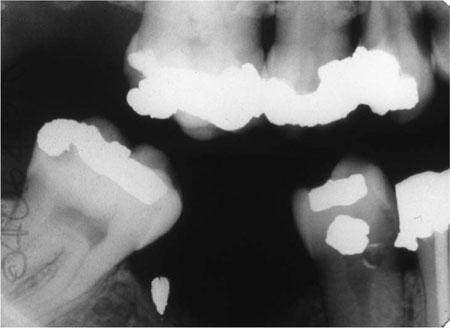

Most indirect restorations are placed to restore the contour, function and appearance of teeth previously restored with plastic restorations. In restoring broken down or damaged teeth with plastic restorations, it is sometimes difficult to achieve appropriate contact areas (Fig 1-1) and occlusal form (Fig 1-2). Indirect restorations such as crowns, onlays and inlays enable the contact areas and the occlusal form to be controlled in the laboratory. The majority of extensive restorations are placed because of primary caries, or caries adjacent to existing restorations. Others will be placed following a fracture of tooth tissue, classically a cusp fracture associated with an occlusoproximal restoration (Fig 1-3). Relatively few extensive restorations are placed as a consequence of trauma.

Fig 1-1 Bitewing radiograph showing a ledge on the amalgam restoration in the LR4. This occurred as the LR4 has an extensive defect, making it difficult to develop a tight contact area while keeping the matrix band adapted cervically.

For a patient with new and secondary caries (Fig 1-5a,b) it is important that treatment is carried out in phases. The first phase should address pain and other immediate problems. Thereafter, care should be aimed at prevention. This stage of treatment should include stabilisation of the lesions and protection with temporary and transitional restorations. This is necessary to ensure that extensive lesions do not progress during the preventive phase of treatment. It also allows a stepwise approach to caries removal.

Fig 1-5 (a,b) A left bitewing radiograph of an 18-year-old patient (a), and four years later (b). This demonstrates that caries risk can change and the dentist should always be vigilant and continually assess risk. This patient’s initial treatment should be pain relief, followed by a stabilisation phase and prevention. Indirect restorations should not be considered until successful prevention has been instituted and caries risk has been controlled.